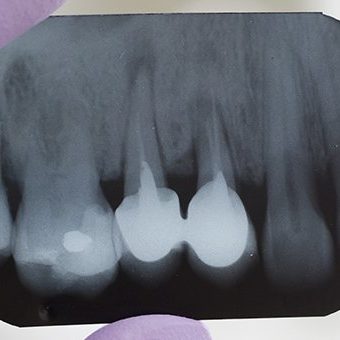

Namen konzervativnega zobozdravstva, ki je temeljna veje stomatologije, je preprečiti vzroke, ki lahko vodijo v izgubo zob.